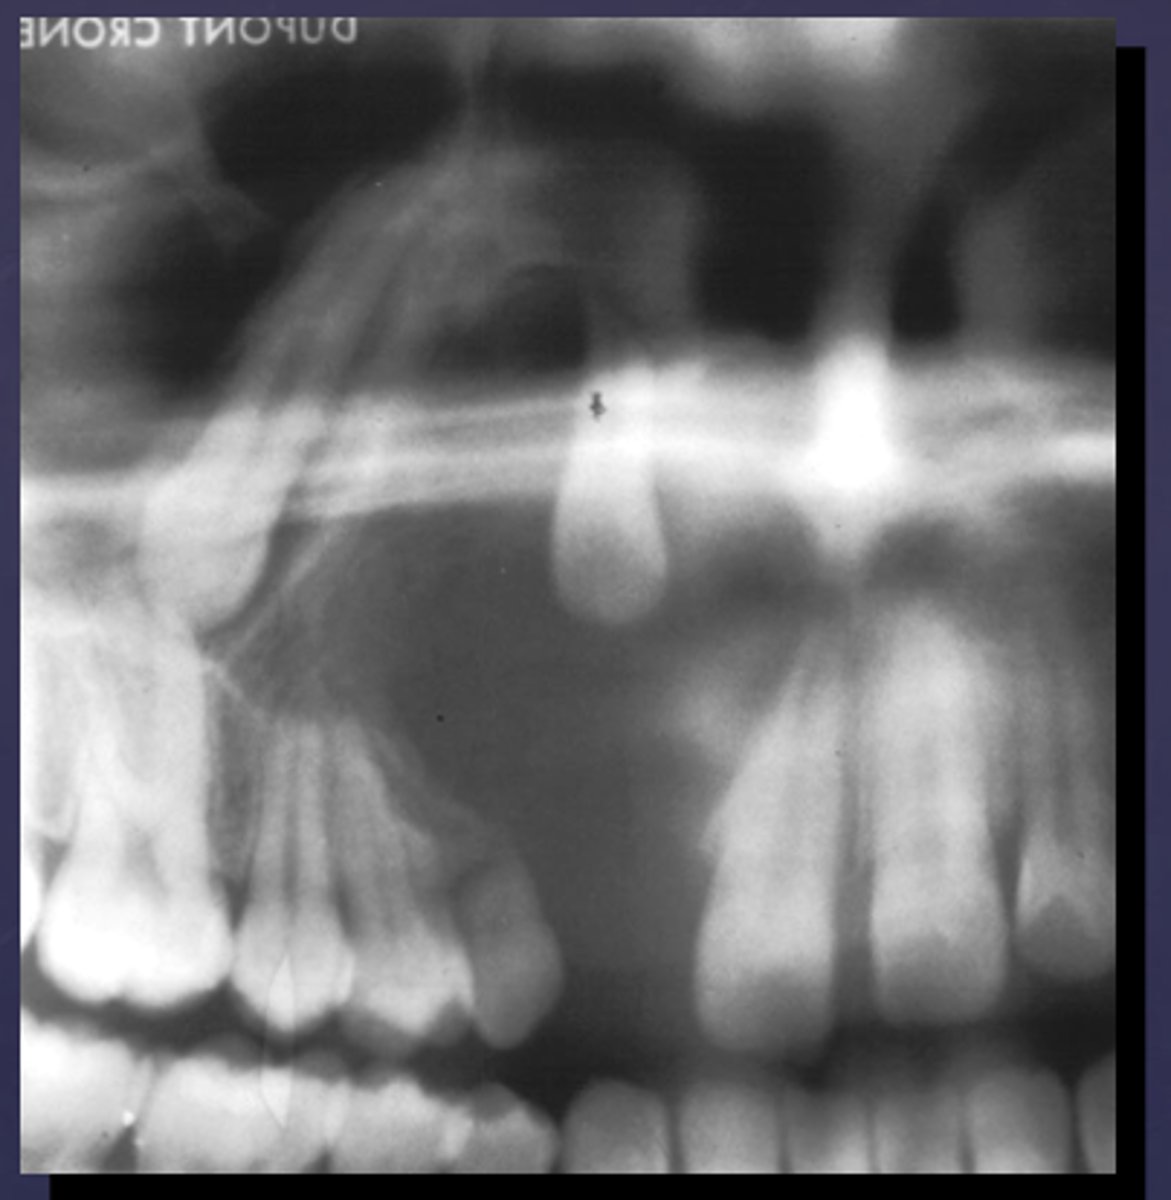

How would you describe the lesion?

- Periapical radiolucency associated with #30

- Has a band of sclerotic change extending from the apical radiolucency to the inferior alveolar canal and beyond

- Furcation involvement

(Furcation involvement as well as a band of sclerotic change extending from the apical radiolucency to the inferior alveolar canal and beyond)

What category would you put this lesion into?

Inflammation

what could be a differential diagnosis for this lesion? (select all that apply)

A. PCOD

B. multiple myeloma

C. apical rarefying osteitis

D. chronic sclerosing osteomyelitis

Also note apical rarefying osteitis #14 ( remnant root fragments, no crown due to caries)